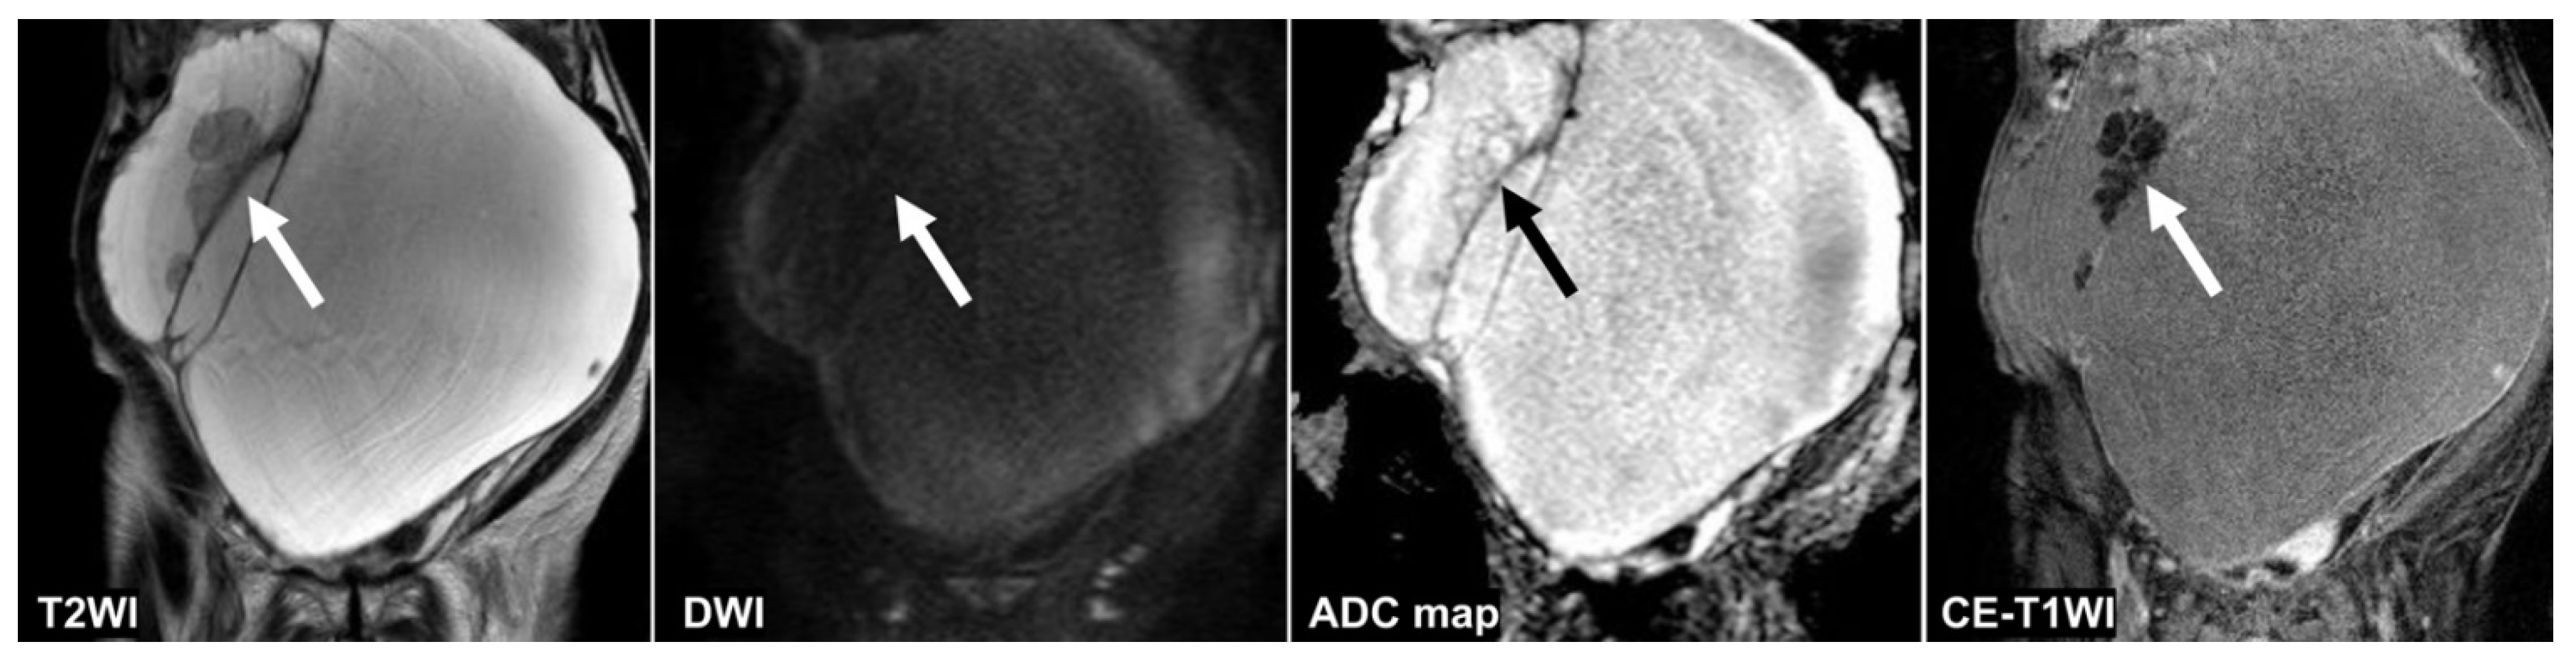

Figure 4, Figure 5 and Figure 6 show the test images of three cases in this study with different interpretations by the CNN and radiologists including the confidence value. Figure 4 and Figure 5 show the cases in which the CNN was able to make the correct diagnosis, although the radiologists had a high rate of false-negative diagnoses. Figure 4 shows a tumor with a slight signal difference between the solid components and the background on the T2WI, DWI, and ADC map. Figure 5 shows a non-malignant tumor containing components that were difficult to distinguish between solid components and mucus on the T2WI; however, the CNN diagnosed it as a non-malignant tumor. Figure 6 shows a case in which the CNN and the radiologists showed false negatives on the sequences other than the DWI, and as for the radiologists, it was assumed that the misdiagnosis was due to the difficulty in distinguishing the solid component of the ovarian tumor from the intestinal tract.

Figure 5.

A 95 year old woman with mucinous cystadenoma. Only the CNN could diagnose non-malignant tumors on the T2WI (CNN confidence value; malignant = 0.0%). The CNN and all radiologists could diagnose non-malignant tumors on the DWI (CNN confidence value; malignant = 0.0%). The CNNs and only one reader could diagnose non-malignant tumors on the ADC map and the CE-T1WI (CNN confidence value: malignant = 0.0% on the ADC map and the DWI). Mucus (arrow) showed intermediate signal intensities and was indistinguishable from solid components on the T2WI. The septum (arrow) appeared dense on the ADC map and the CE-T1WI, making it difficult to distinguish it from the borderline tumor. ADC: apparent diffusion coefficient; CE-T1WI: contrast-enhanced T1-weighted imaging; CNN: convolutional neural network; DWI: diffusion-weighted imaging; T2WI: T2-weighted imaging.